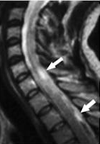

L'hermitte's sign - a rapid resolution

Lhermitte's sign conventional explanation:

"sometimes called the Barber Chair phenomenon, is an electrical sensation that runs down the back and into the limbs. In many patients, it is elicited by bending the head forward. It can also be evoked when a practitioner pounds on the posterior cervical spine while the neck is flexed; this is caused by involvement of the posterior columns. The sign suggests a lesion of the dorsal columns of the cervical cord or of the caudal medulla."

Please read the post to find a possible cure.